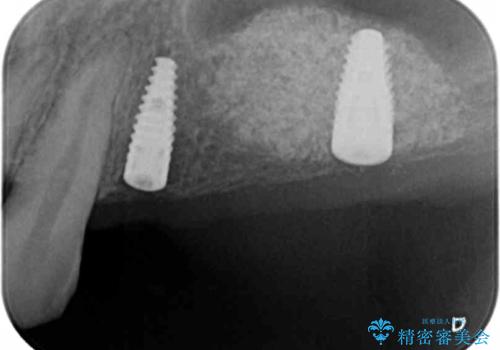

残存している小臼歯も虫歯が大きく保存が難しいため抜去を行い造骨を含めたインプラント治療を行います。

- 112万円(仮歯×3・ストローマンインプラント×2・チタンカスタムアバットメント×2・フルジルコニアクラウン×3・サイナスリフト)(税込)費用は治療当時の料金となります

しっかりと造骨を行ったことでインプラント周囲には十分な量の骨が存在し安定したインプラント周囲環境を整えることができました。